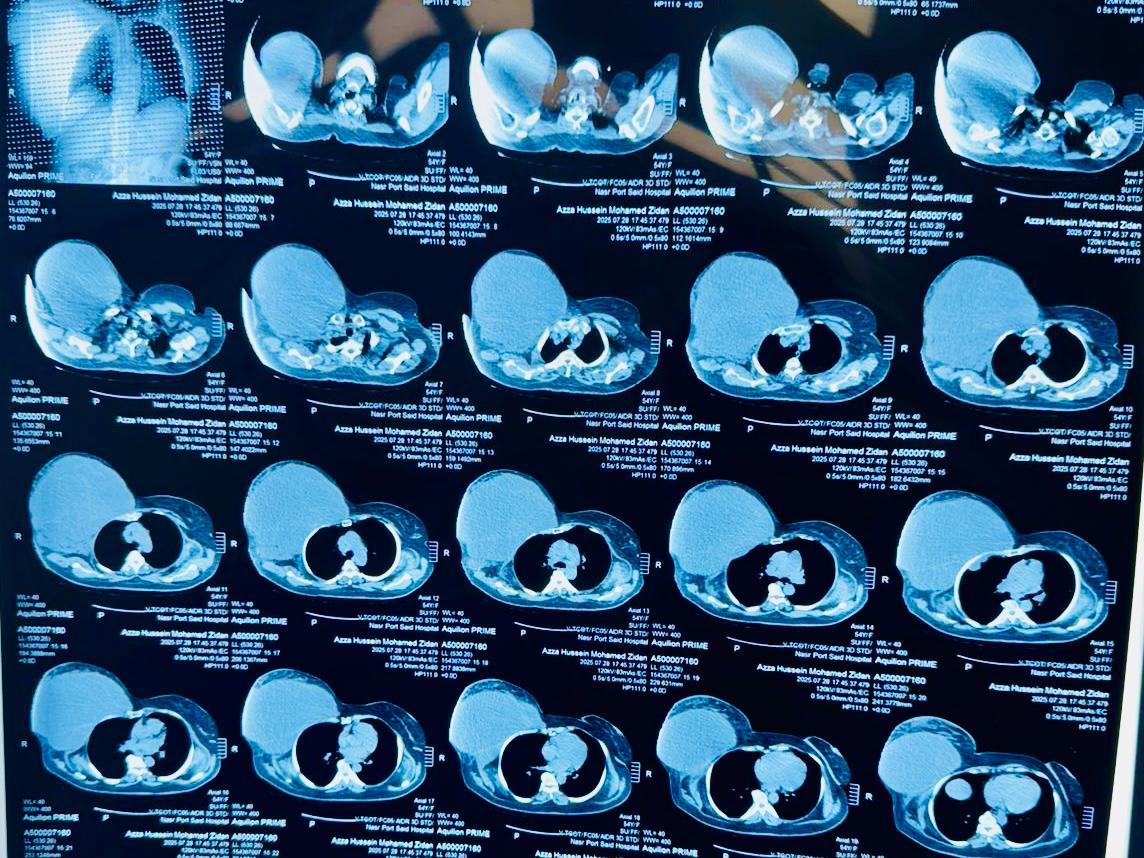

هذا، وتعود تفاصيل الحالة إلى استقبال مستشفى السلام ببورسعيد لسيدة تبلغ من العمر خمسًا وخمسين عامًا كانت تعاني من ورم ضخم في جدار الصدر بلغ حجمه أربعين في ثلاثين سنتيمترًا واستمر أكثر من ثمانية أشهر بعد رحلة طويلة من المعاناة تنقلت خلالها بين عدد من المستشفيات دون جدوى، وبمجرد دخولها المستشفى بادر الفريق الطبي بوضع خطة علاجية متكاملة انتهت بإجراء العملية بنجاح كامل واستئصال الورم مع إعادة بناء القفص الصدري باستخدام أحدث التقنيات الطبية، وقد استغرقت العملية عدة ساعات متواصلة بمشاركة فريق طبي متعدد التخصصات في جراحة الأورام والجراحة العامة وجراحة التجميل والتخدير والعناية المركزة.

وخرجت المريضة من المستشفى بعد أربعة أيام فقط من المتابعة الدقيقة بالعناية المركزة وهي في حالة صحية مستقرة، وتخضع حاليًا لبرنامج متابعة مستمر للاطمئنان على حالتها وضمان تعافيها الكامل، ويُعد هذا التدخل من العمليات النادرة والمعقدة نظرًا لضخامة الورم وموقعه الحساس.